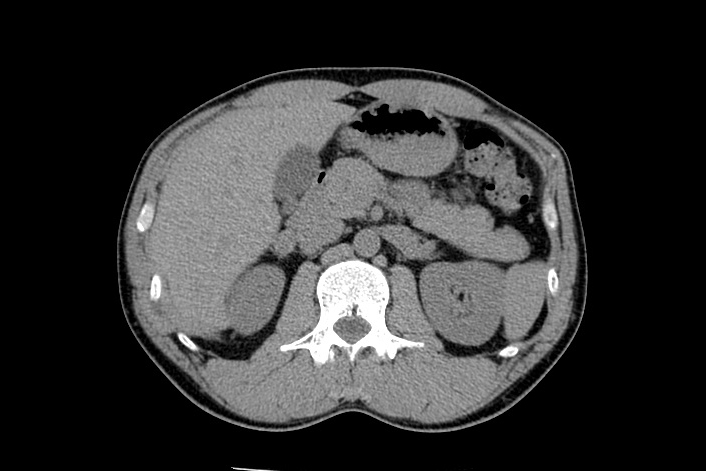

腹部CT

腹部CTでは、上腹部臓器(肝臓、膵臓、胆のう、腎臓など)の診断に優れ、骨盤内臓器(女性:子宮卵巣、男性:前立腺)を含めた腹部全体を写し出します。超音波検査では見えにくい、深部臓器(特に膵臓)の描出が可能になります。